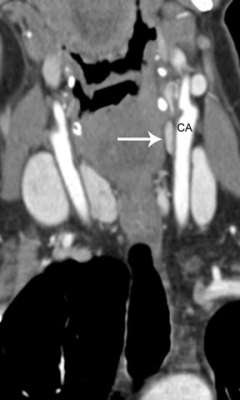

Axial 4D-CT image showing parathyroid adenoma

Axial 4D-CT image showing parathyroid adenoma in the upper chest, behind the sternum (breastbone).